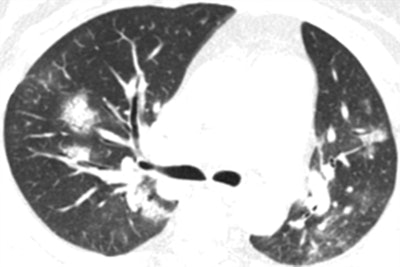

Among the patient cohort, the most common CT findings were ground-glass opacities and consolidation with or without vascular enlargement (96.1% of patients), followed by interlobular septal thickening (70.6%), air bronchogram sign (68.6%), and air trapping (11.8%). Most of these findings were similar to CT features previously reported in patients with severe acute respiratory syndrome (SARS) and Middle East respiratory syndrome (MERS).

The researchers did identify CT findings that distinguished COVID-19 from SARS and MERS in several cases: the presence of a reversed halo sign in 3.9% of patients and pulmonary nodules with a halo sign in 17.6%. In addition, COVID-19 patients more frequently had multifocal involvement on CT, compared with unifocal involvement for SARS and MERS.